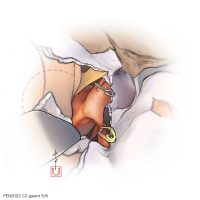

監修:谷川 緑野 / 札幌禎心会病院脳卒中センター

FEN2022シリーズ

術後イラストシリーズ